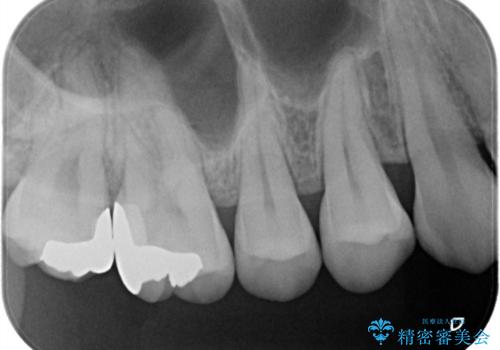

他院で入れたインレーの下にむし歯、ゴールドインレーで修復

拡大視野下で虫歯を除去し、ゴールドインレーにて修復治療を行なっております。

ゴールドインレーは適合もよく、材料が欠けたり腐食するリスクも極めて低い安定した治療法です。